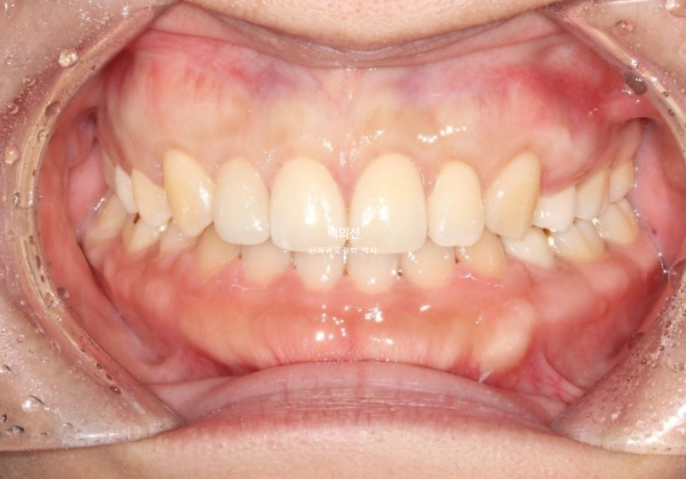

드디어 25년 7월, 2년의 교정치료를 마무리 합니다.

이제 클리피씨 브라켓을 떼고 잇몸성형과 왜소치 라미네이트를 할 차례입니다.

왜소치에 무삭제 라미네이트까지 들어간 모습입니다.

어느쪽이 자연치이고 어느쪽이 왜소치 라미네이트 일까요?

정답은 파란 화살표 치아가 바로 젤라미입니다.

어금니 교합은 물샐틈 없이 좋습니다.

비대칭으로 인해 어긋났던 중심선이 맞아졌습니다.

교정만으로 턱뼈의 비대칭을 바꿀 순 없지만 최소한 치아중심선은 정확히 맞춰줄 수 있습니다.

교정 후 사진에서 앞니 교합이 다소 깊게 물리는 게 보이시죠?

의도한 부분이며 초진 시 앞니 물리는 게 얕으면, 재발을 고려하여 정상보다 좀 더 깊게 물리게 마무리 하는 게 좋습니다.